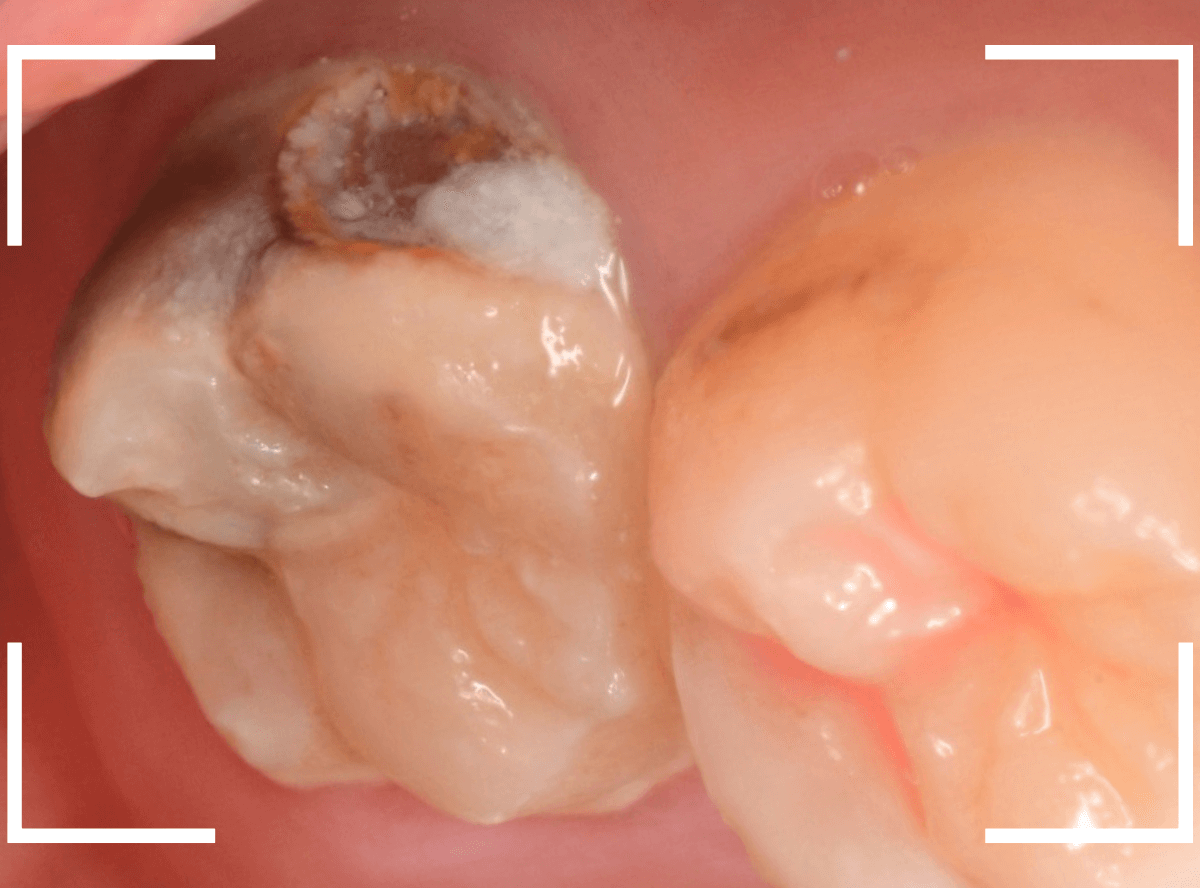

Case.6 上の奥歯の、見えづらいところで虫歯が進行!

こちらも上の一番奥の歯が深い虫歯になってしまった方です。

歯の頬側から奥側にかけて大きな虫歯になっているのがわかります。

カメラではうまく撮れましたが、実際は歯ブラシが届きづらく、虫歯になりやすいところです。

頬側の写真です。

ボコッと虫歯で穴が空いている状況ですが、本人には自覚症状がありません。

自覚症状がないから問題ないわけではない、というのがわかりますね。

治療を開始すると、大きな虫歯が出てきました。

虫歯を全て除去したところです。

赤い小さな点が見えているのは、歯の神経が少し見えてしまっている状態です。

運が悪ければ、神経を取る治療が必要になるかもしれません。

神経を保護するお薬をつめ、セメントで蓋をして、しばらく経過観察をします。

あとは痛みが出ないように祈ります。。。